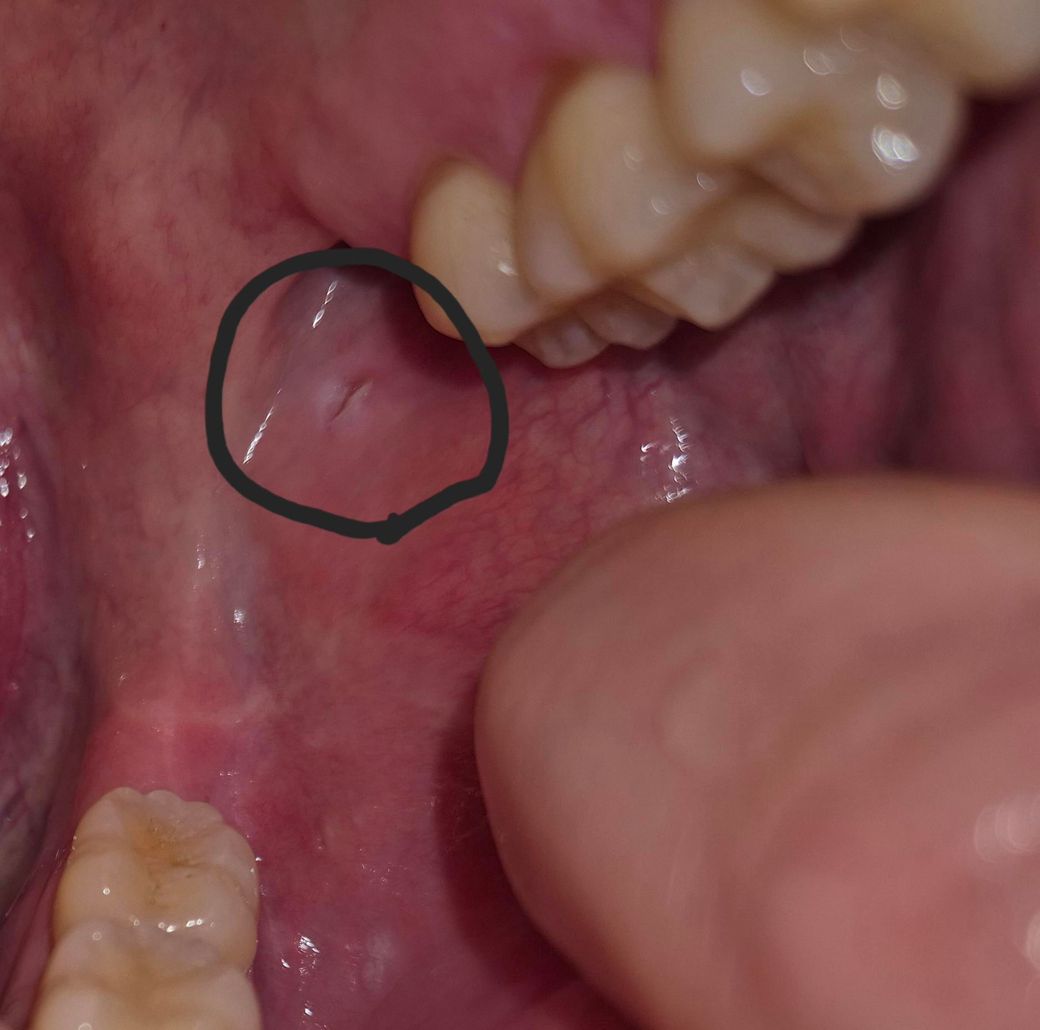

오래 지속되면 구강암이될 가능성이 있다는데 일단 사진 첨부합니다.

• 1번 째 사진

말씀 주신 경과와 기저질환을 종합하면 단순 재발성 구내염로만 보기에는 주의가 필요합니다.

볼 안쪽 점막 병변이 6주 이상 지속되고 크기나 모양 변화 없이 아물지 않는 경우, 감별해야 할 범주는 크게 세 가지입니다. 첫째, 만성 외상성 궤양입니다. 씹힘, 날카로운 치아, 교정물, 이를 악무는 습관 등 반복적 자극이 원인이며 통증이 거의 없을 수 있습니다. 둘째, 면역조절제 관련 점막 병변입니다. 휴미라(adalimumab)는 종양괴사인자 억제제로, 감염에 대한 국소 면역 반응을 약화시켜 구강 궤양의 장기 지속, 진균·바이러스 감염, 비특이적 염증 병변이 오래 가는 경우가 있습니다. 셋째, 비교적 드물지만 반드시 배제해야 할 구강 편평상피암 또는 전암성 병변입니다. 통증이 없고, 단단하게 만져지거나, 가장자리가 불규칙하거나, 2주에서 3주 이상 치유 경향이 없는 경우에는 조직학적 확인이 원칙입니다.

현재처럼 1달 반에서 2달 지속되었고, 면역억제제 사용 중이며, 최근 수술 병력까지 있는 경우라면 “경과 관찰” 단계는 이미 지났다고 보는 것이 보수적입니다. 구강암으로 바로 단정할 근거는 부족하지만, 배제를 위해서는 조직검사가 필요할 수 있습니다.

진료과 선택은 이비인후과 또는 구강악안면외과가 적절합니다. 일반 치과보다는 구강 점막 병변 평가와 필요 시 생검이 가능한 곳이 좋습니다. 이비인후과에서도 구강 점막 병변에 대한 진찰과 조직검사가 가능합니다. 방문 시 휴미라 사용 중이라는 점과 병변 지속 기간을 반드시 말씀하시는 것이 중요합니다.

정리하면, 통증이 없더라도 6주 이상 지속되는 구강 점막 병변은 정상 소견으로 보지 않으며, 특히 종양괴사인자 억제제 사용 환자에서는 조기 평가와 필요 시 조직검사가 권고됩니다. 빠른 시일 내 이비인후과 또는 구강악안면외과 진료를 권합니다.

• 사진의 소견 및 이야기 하신 내용만 놓고 심각한 소견일 가능성이 높아 보이거나 하지는 않습니다만 구내염이 지속되는 것이 길어진다면 한 번 평가를 받아보는 것이 안전하긴 하겠습니다. 관련하여서는 일차적으로는 이비인후과로 가는 것이 가장 적절할 것으로 사료됩니다.